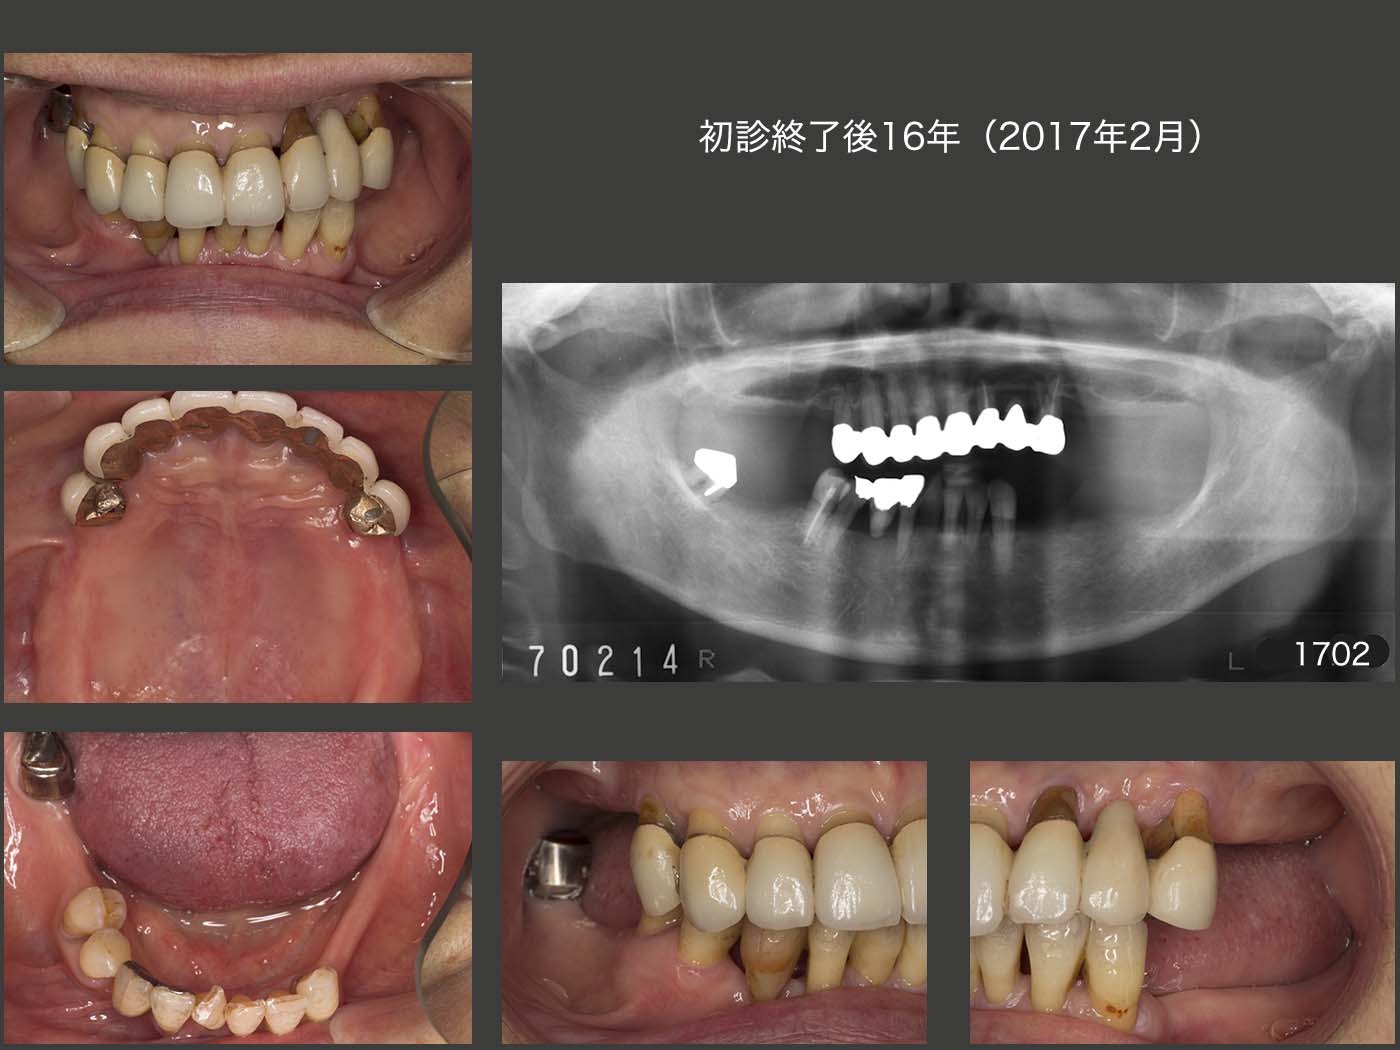

2017年2月,初診終了後16年の状態.スライド5で述べたマイナーチェンジを時々行ったが,全体としては良好に推移している.特に,メタルボンド冠で連結固定した上顎の残存歯が,まだ十分に機能していることに驚いている.

初診終了後16年の義歯装着の状態.レストの適合は16年の月日が流れたとは思えないぐらいに良い状態である.特に上顎義歯は,下顎の残存歯と咬合していないのが故に,顎堤の吸収が生じなかったと考えている.(残存歯による加圧要素がないと,顎堤は吸収しにくい.)もちろん,上顎義歯はこれまでに一度もリライニングを行っていない.

スライド下段に示す,初診終了後約20年の2020年11月の状態であるが,右下2の動揺が大きい以外は,大変良好である.